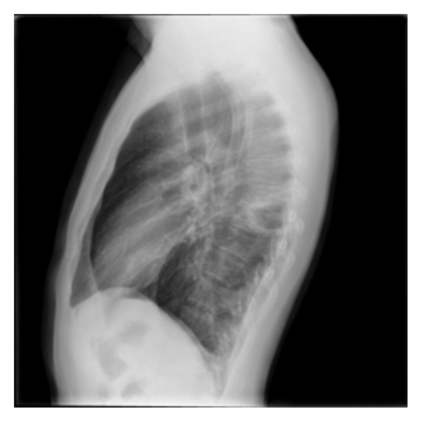

The evaluation of infectious disease processes on radiologic images is an important and challenging task in medical image analysis. Pulmonary infections can often be best imaged and evaluated through computed tomography (CT) scans, which are often not available in low-resource environments and difficult to obtain for critically ill patients. On the other hand, X-ray, a different type of imaging procedure, is inexpensive, often available at the bedside and more widely available, but offers a simpler, two dimensional image. We show that by relying on a model that learns to generate CT images from X-rays synthetically, we can improve the automatic disease classification accuracy and provide clinicians with a different look at the pulmonary disease process. Specifically, we investigate Tuberculosis (TB), a deadly bacterial infectious disease that predominantly affects the lungs, but also other organ systems. We show that relying on synthetically generated CT improves TB identification by 7.50% and distinguishes TB properties up to 12.16% better than the X-ray baseline.